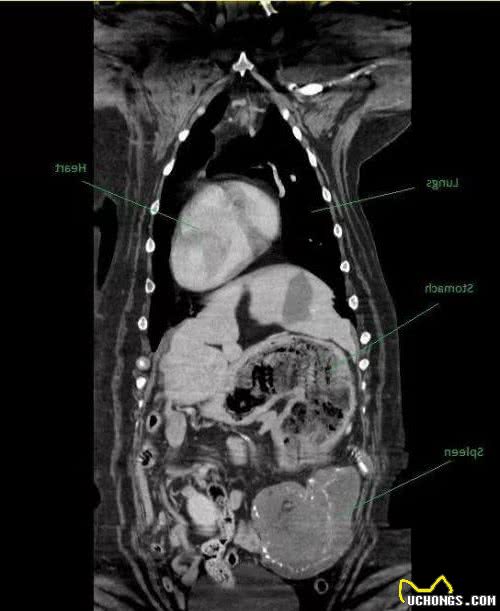

这部电影显示,迈西脾脏附近有相当大的肿块。医生说这很可能是恶性肿瘤。主人很担心,她立即同意给迈西做手术。

当医生切开迈西的胃时,他发现情况并非如此。仔细一看,发现不是肿瘤,而是泰迪熊和毛绒玩具!